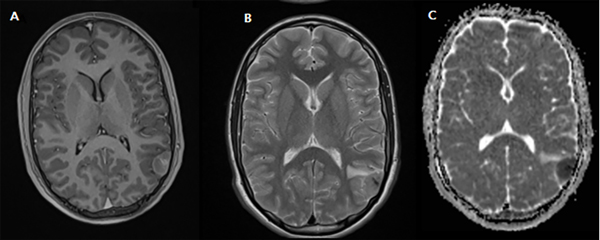

Durante el procedimiento, se coloca al paciente en decúbito dorsal con la cabeza lateralizada hacia la derecha. Se realiza abordaje parietal izquierdo y, luego de extraer la plaqueta ósea, se evidencia la duramadre también intacta. Se decide por una ecografía intraoperatoria para localizar la lesión. En la misma se observa una imagen hiperecoica sin bordes definidos en el centro del campo. Luego de la apertura dural, se localiza la lesión intraaxial con expresión cortical, de bordes no definidos, infiltrante, sin plano de clivaje (Fig. 2). Esto no era compatible con lo que esperábamos encontrar acorde a los estudios prequirúrgicos. Se lleva a cabo la resección en bloque con márgenes libres y control por anatomía patológica.

Figura 2: Imagen intraquirúrgica. Se evidencia lesión cortical infiltrativa de bordes no definidos con centro necrótico.